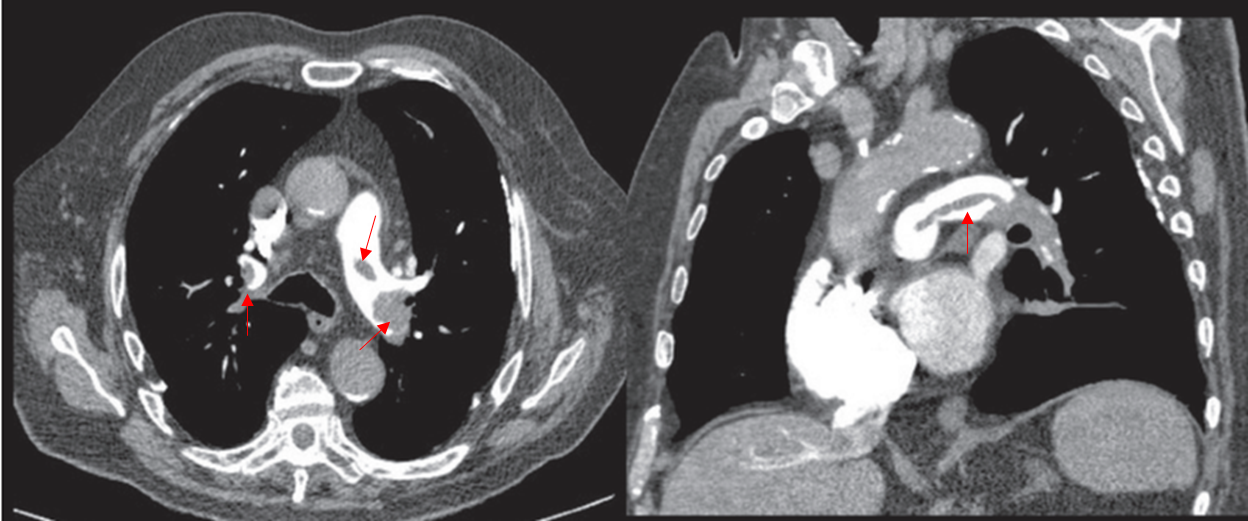

Img | Chest CT: 양측 폐동맥 혈전 |

급성 호흡곤란, 교통사고 과거력, CT상 혈전이 있으므로 PTE이다. PTE 예방을 위한 약제는 heparin 등의 anticoagulant이다.

• CT에서 폐동맥 혈전이 보이므로 폐색전증으로 진단할 수 있다.